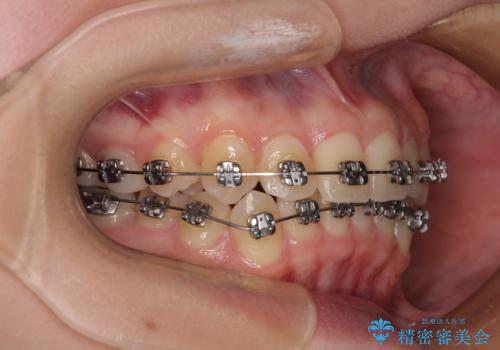

前歯のクロスバイト ギラギラのワイヤー装置で矯正治療

- 矯正装置

- メタルブラケット

- 前歯のクロスバイトを改善したいとのことで来院された患者様です。

マウスピース矯正では前歯の神経への負担が大きいことを懸念され、ワイヤー装置による矯正治療を行うこととしました。

クロスバイトが改善する際は、前歯しか接触しないため、痛みがあったり食事が取りにくかったりと、不便な時期がありますが、1年強の短期間で無事に治療を終えることができました。